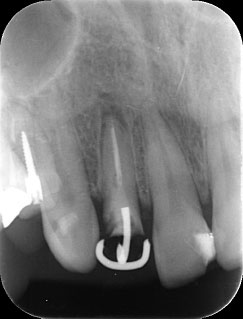

MTM開始直後と、終了後です。フックの位置が変わっているのがわかると思いますが、それが歯が動いた証拠となります。

歯からはフック、隣り合った歯にはワイヤーが渡してあります。そこにゴムをひっかけて歯を挺出させます。